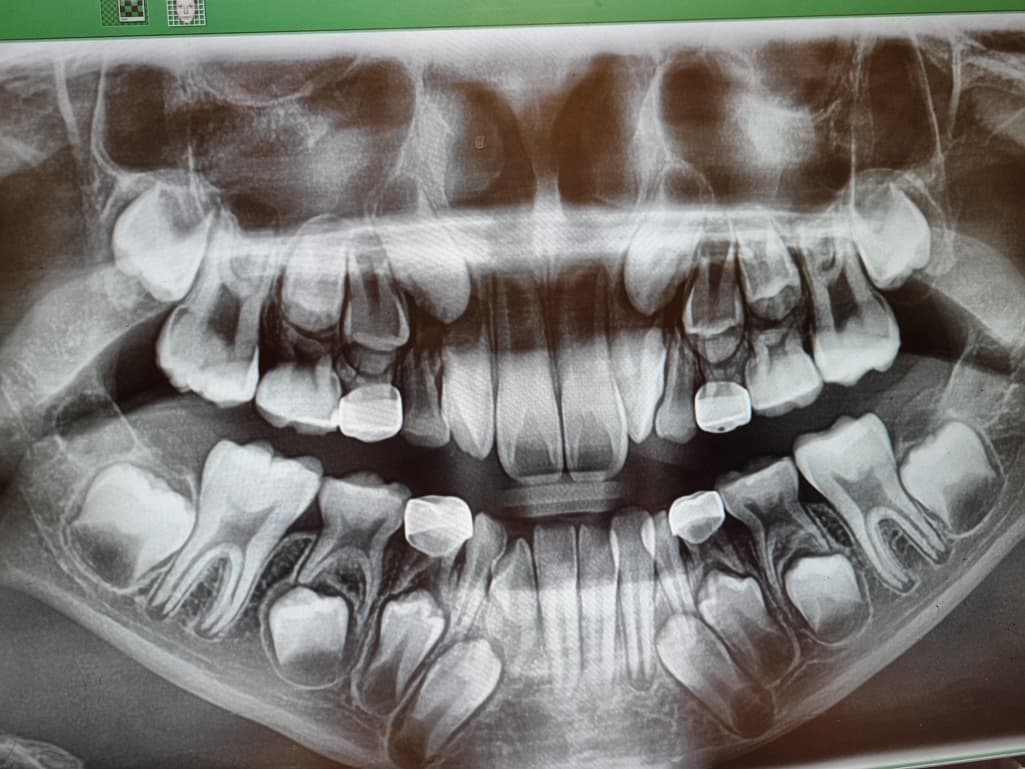

엑스레이상 송곳니가 삐뚤한데 교정이 필요할까요?

첫니도 돌지나서 날만큼 늦어서 그런지 아직 유치가 다 빠지지않았습니다~근데 치과진료를 가니 엑스레이상 송곳니 방향이 좀 문제가있어보인다고 교정전문병원에가서 상담을 한번 받아보라고하네요..